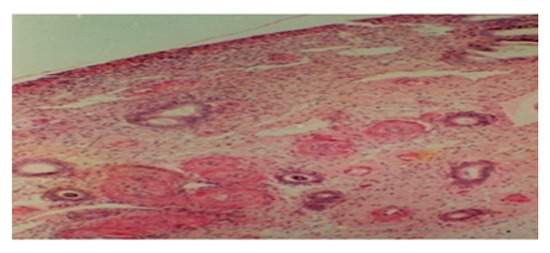

3.3. From 10th Postpartum Day

3.4. From 11th to 14th Postpartum Day